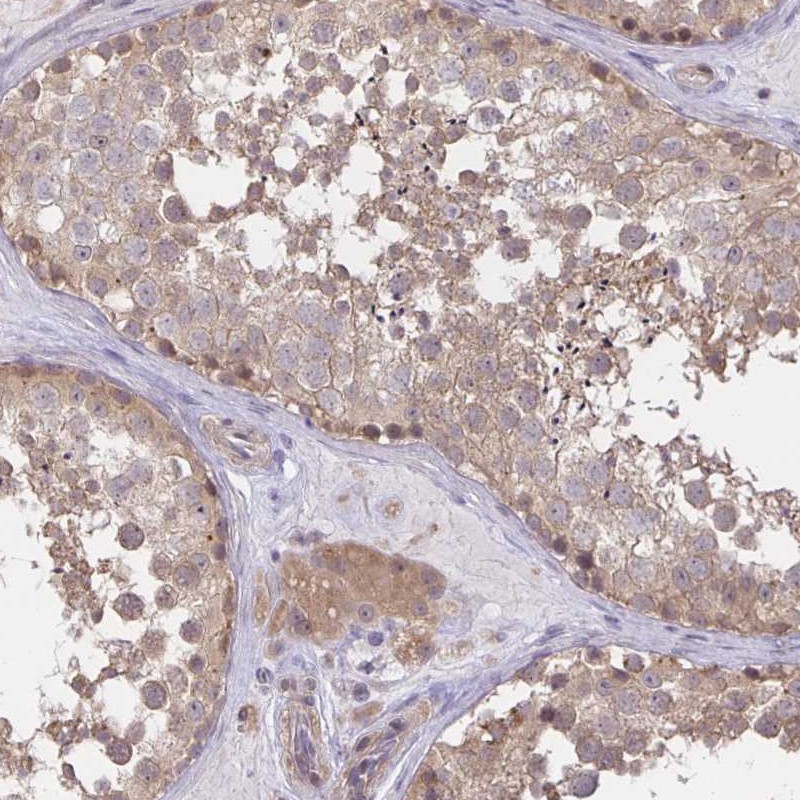

MIEN1